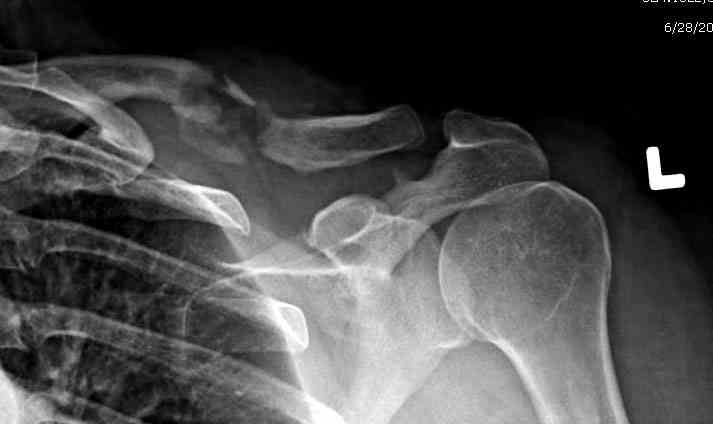

Недавно разбирали случай ложного сустава.

45 летная женщина после автоаварии, алкоголь 163 и 20 летним стажем курения.

Консервативное лечение, через 8 мес. операция Rockwood pin с костной пластикой в нашем городе другим врачом. После 8 недели падение, гвоздь удален оперирующим хирургом, больная направлена к нам. Фиксация реконструктивной пластиной с трикортикальным графтом, добавлен BMP-2. Для стабилизации фиксацию провели через акромион.

Вот уже два месяца больная также продолжает жаловаться на боли, буквально на днях удалили акромиальную часть пластины с специальной пилой с алмазным покрытием для медицинского металла. До сих пор судьба ложного сустава неизвестна....